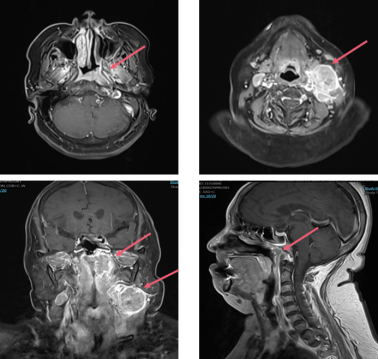

2024年9月2日 鼻咽部+颈部MR:左侧顶后壁及咽隐窝可见椭圆形软组织肿块,最大层面约18×24×27mm;病灶略向外后突入左侧咽旁间隙内份,侵犯左侧腭帆张提肌、椎前肌。左侧咽后间隙及双侧颈部多发肿大淋巴结,以左侧Ⅱ区较多较大,大者约31×35mm。颅底、斜坡骨质未见异常信号。双侧上颌窦及蝶窦少许炎症;左侧乳突炎症。

image.png